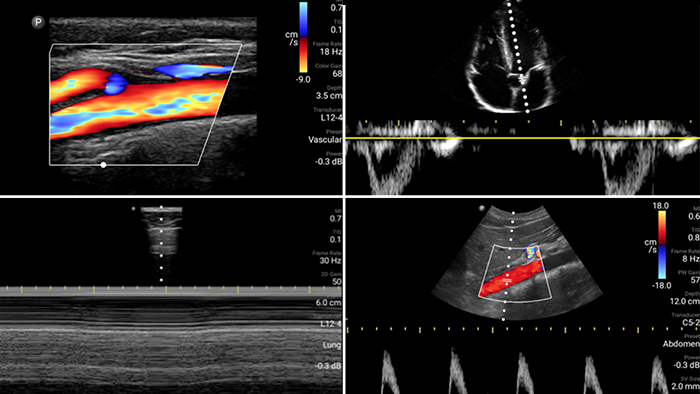

First case image

Lumify is with you

every step of the way

Evaluate, diagnose and treat your patients in

minutes with a multi-point POCUS exam.